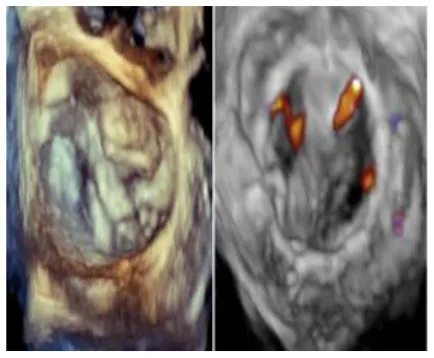

No left ventricular outflow tract obstructions were detected due to the presence or dislocation of the TAVI prosthesis (mean LVOT gradient of 8 ± 1 mmHg). We were able to fix a mild residual leak between the Sapien and the pericardial skirt in two out of five patients using intraoperative transesophageal echocardiographic control (3D zoom with color, “en face” or “surgical” projection of the MV).